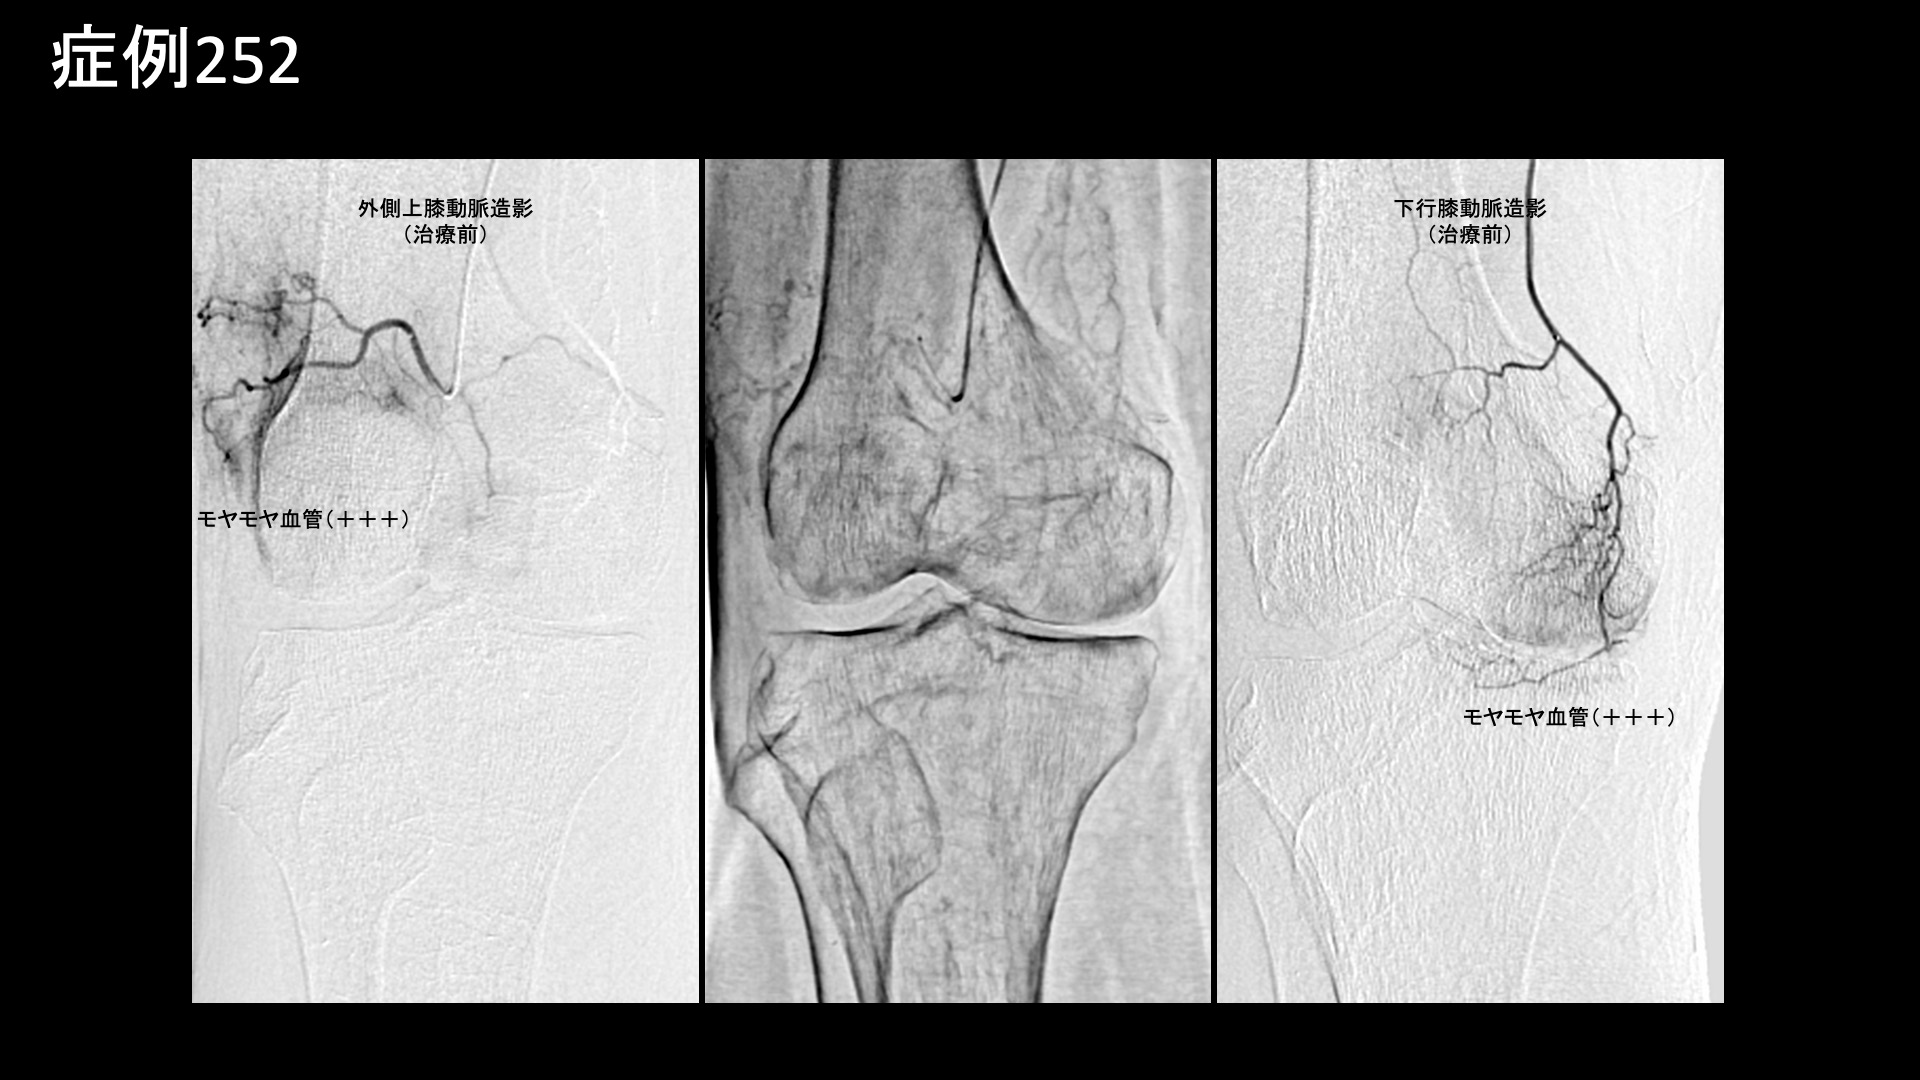

膝:変形性膝関節症など 【70代:男性】急激に悪化した膝の痛みで歩けなくなり夜も寝られず水も溜まる・・ネフローゼ症候群を合併した変形性膝関節症の実例(変形性膝関節症、ネフローゼ症候群) 2025.12.01 鴨井院長による動画解説 受診までの経過 それまで痛めたことはなかったのですが、3ヶ月前から急に右膝が痛み始めました。整形外科を受診し、水を抜いてもらいヒアルロン酸注射を受けていましたが改善しませんでした。松葉杖を使うほどの痛みにもなり、安静時にも痛むようになりました。ついには夜間に痛みで目が覚めるほどになりました。鎮痛薬も効かない一方で、外科手術の適応ではないと言われ思い悩んでいたところ、当院の治療を知り受診されました。 既往疾患;ネフローゼ症候群 診察時の所見 杖歩行にて入室されました。レントゲンでは中等度以上(KL分類3相当)の関節変形を認めました。エコー検査では、膝蓋上嚢に中等度以上の水腫を認め、その周囲や滑膜組織には炎症によるモヤモヤ血管を反映した異常血流信号が豊富に認められました。変形性膝関節症の診断ですが、病状は重症でした。基礎疾患としてのネフローゼ症候群が少なからず影響を与え、炎症が助長されていることが示唆されました。非常に強い炎症が関与していることから良い治療適応と判断し、モヤモヤ血管(病的新生血管)に対する運動器カテーテル治療(微細動脈塞栓術)を受けていただきました。 治療の所見 血管造影を行うと、外側上膝動脈、下行膝動脈などでモヤモヤ血管が濃染像として描出されました。治療後は画像上速やかに消失しました。その他複数箇所の治療を行い終了しました。 尚、強い炎症を反映して、治療時の再現痛は強めでした。 *再現痛とは、薬液投与時に普段の痛みが一定程度再現される現象です。責任血管の同定のための参考とします。 治療後の経過 治療翌日から改善しました。治療後3週間では、ほとんどの痛みが無くなりました。肩関節の可動域も完全に回復し、バンザイもできるようになりました。半年間苦しんでいた痛みのあまりの回復ぶりに、『最初からここに来ればよかった』と話されるほどでした。エコーで確認すると、まだ石灰沈着については大きな変化はありませんでしたが、今後吸収されていくことも期待できます。非常に経過良好であったことから、終診となりました。石灰沈着性腱板炎は強い炎症を伴っていることが多く、その苦痛も五十肩以上になることが少なくありません。カテーテル治療は強い炎症にこそ、強い効果を発揮します。実際に、本症例では非常に早期から快復しました。罹病期間が長くなければ、石灰も吸収されて無くなります。 非常に良い適応疾患の一つですので、お悩みの方はぜひご検討いただくと良いと思います。 治療前画像:損傷を受ける、あるいは繰り返しのストレスにより発生した異常な新生血管 治療後画像:カテーテルを用いて塞栓物質を血管内に投与し新生血管を塞いだ状態 治療費用:治療する部位によって費用が異なりますのでこちらをご参照ください。 主なリスク・副作用等:針を刺した場所が出血により腫れや痛みを生じたり、感染したりすることがあります(穿刺部合併症)。造影剤によるアレルギー(皮膚のかゆみ・赤み・息苦しくなるなどの症状)が出ることがあります。 変形性膝関節症の詳細 【50代:男性】最初からここに来ればよかった・・ステロイド注射無効で半年間苦しんだ石灰沈着性腱板炎による肩の痛み(石灰沈着性腱板炎、肩関節周囲炎) 前の記事 【40代:男性】新型コロナウイルスワクチン接種後、3年に亘り続いたしつこい肩の痛み。石灰沈着性腱板炎後遺症に対するモヤモヤ血管治療(石灰沈着性腱板炎後遺症、SIRVA、新型コロナウイルスワクチン接種) 次の記事